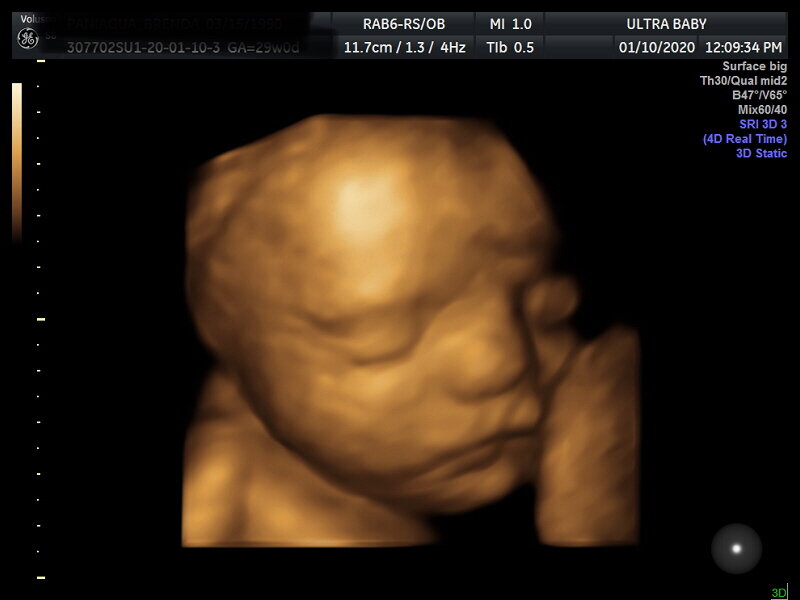

4D Examples